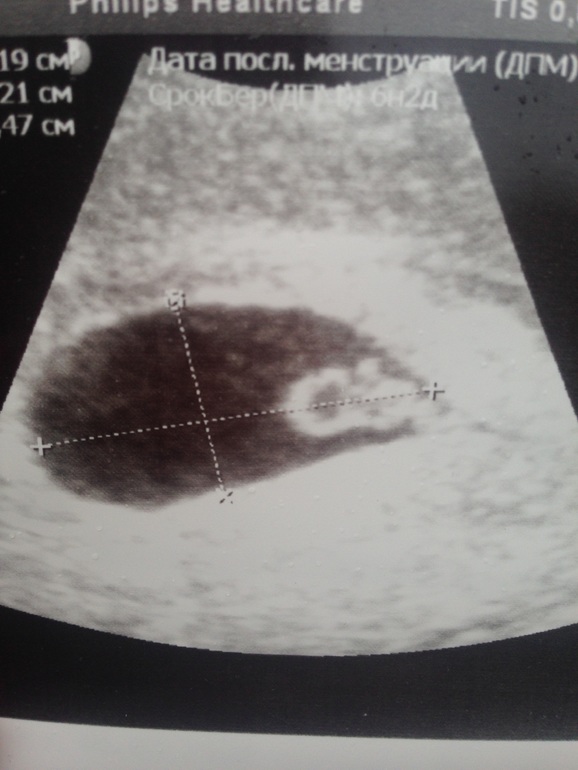

Я была в 6н5д. От зачатия было 4н2д. Сердцебиение увидели, мне показали) эмбриончик тоже, КТР 5,6 мм. В заключении написали Б 4-5 недель. От О так и получается))

dee71d3627d413032a398de5a73adc3d.jpg 9aedcc1f06b9d387c3249e403123ad50.jpg Первое фото в 6н5д, там слева эмбрион, а справа как кружочек желточный мешок, второе фото вчера